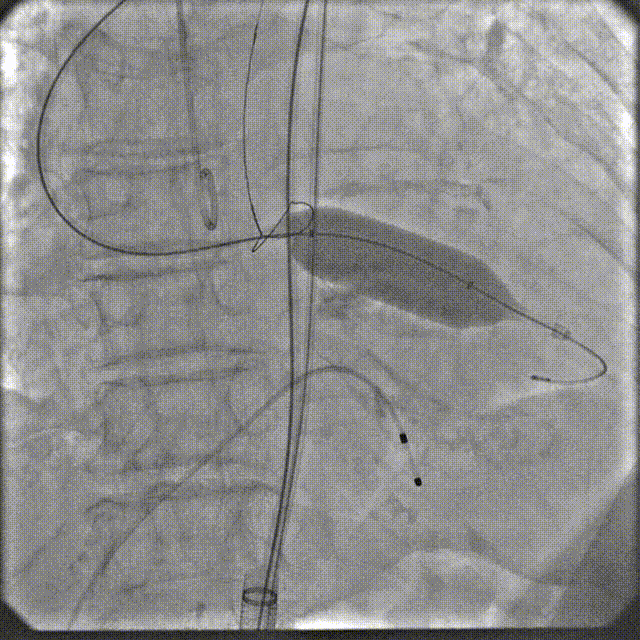

3月30日上午,培训班在重大疾病新药靶发现及新药创制全国重点实验室模式动物工程研究中心开展TAVR手术实操训练,二尖瓣缘对缘修复术器械演示。全体学员在符合GLP标准的实验环境中,使用经病理建模的实验猪进行介入操作演练。该动物模型通过专业培育,其主动脉瓣钙化程度与血流动力学参数可复现人类重度主动脉瓣狭窄的核心病理特征。

在数字减影血管造影(DSA)与经胸超声(TTE)双模影像引导下,学员系统完成经导管主动脉瓣置换术全流程操作:首先建立经皮腹主动脉穿刺入路,随后进行导丝跨瓣定位,继而操控人工瓣膜输送系统,最终实现瓣膜精准释放。训练重点强化三个技术维度:①血管入路建立与并发症预防 ②影像引导下的器械递送路径规划 ③基于实时超声的血流动力学评估。

通过标准化动物实验平台,参训医师不仅掌握了TAVR手术的核心操作规范,更深入理解了影像学参数与解剖结构动态匹配的决策逻辑。该训练体系通过量化评估穿刺成功率、瓣膜定位精度及操作时效性等核心指标,为临床技术转化建立可追溯的质量控制标准。